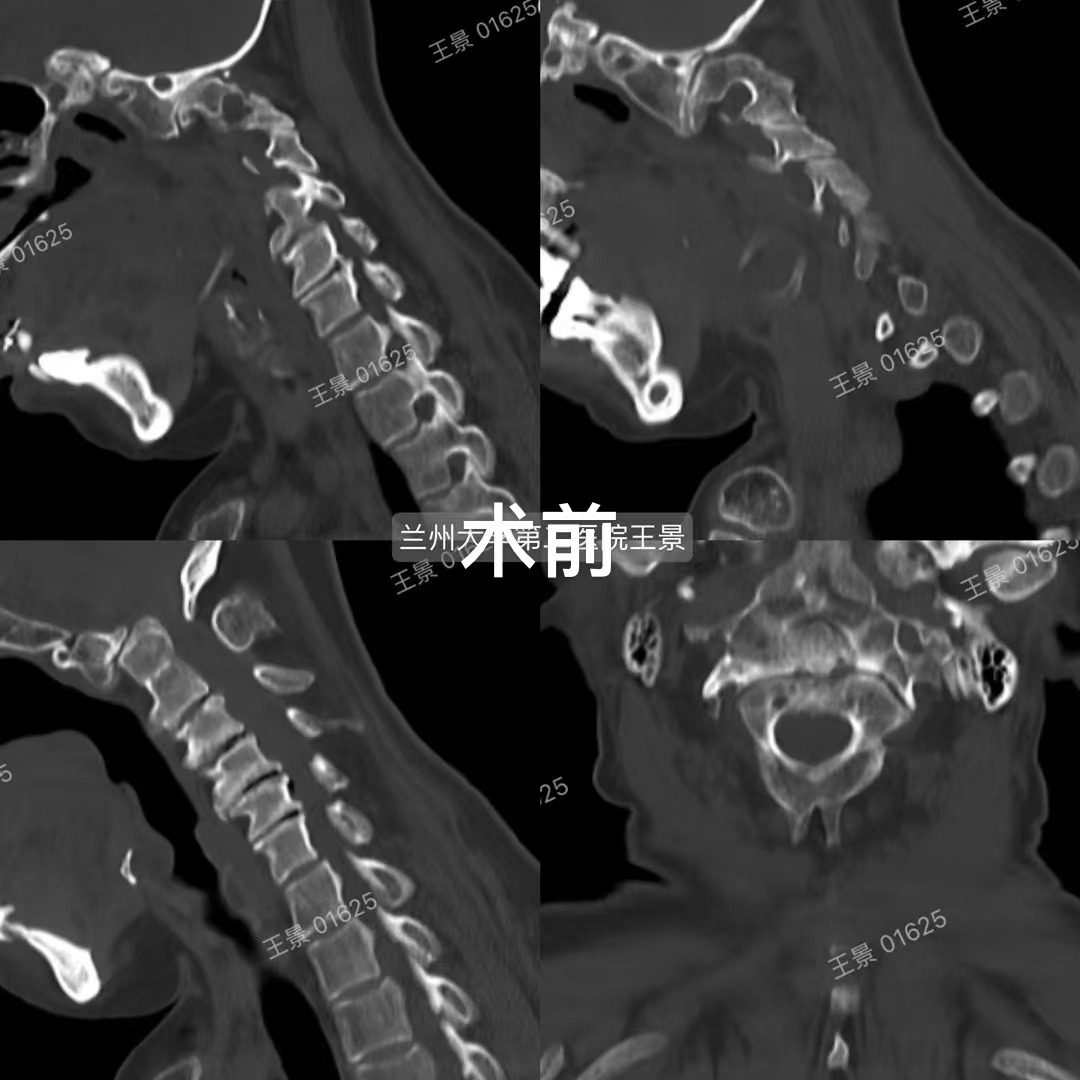

寰枢椎即第一、二颈椎,位于颅颈交界区,解剖结构复杂,毗邻延髓、椎动脉,且常常产生变异,手术难度和风险极高。寰枢椎脱位是由于多种病因使得寰枢关节失去正常对合关系,造成寰枢椎畸形脱位,脊髓压迫。引起颈不适、活动受限、四肢麻木无力、瘫痪以及吞咽困难等症状。严重者压迫呼吸循环中枢进而危及生命,全国仅少数大型三甲医院可开展寰枢椎脱位的矫形手术。

兰大二院骨科王景团队在既往治疗难复性寰枢椎脱位及颅底凹陷的经验和基础上,已完成多例显微镜辅助下难复性寰枢椎脱位的后路松解、椎间隙撑开复位融合技术,均取得良好效果。这项新技术在不需要外在牵引的情况下,使大部分难复性寰枢椎脱位得到了快捷安全有效的治疗,寰枢椎关节间融合也为颅颈交界区畸形手术提供了强有力支撑和有效融合界面。